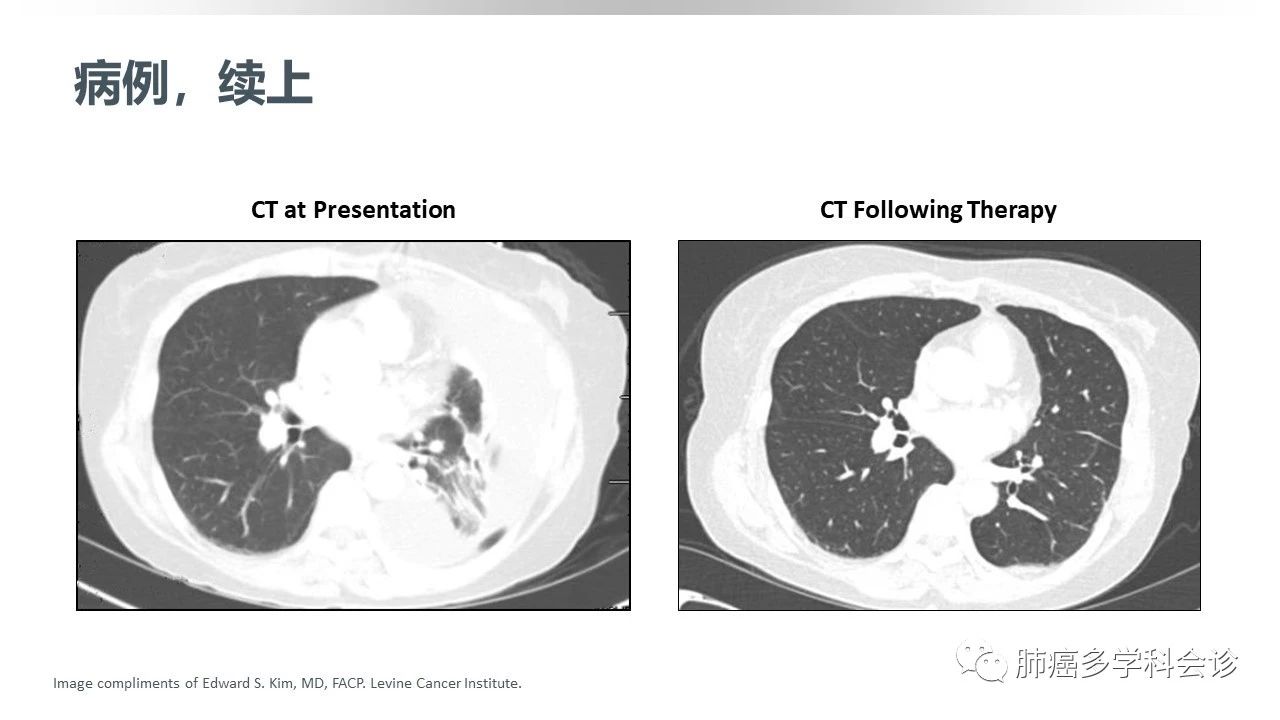

ALK易位阳性NSCLC的一线治疗